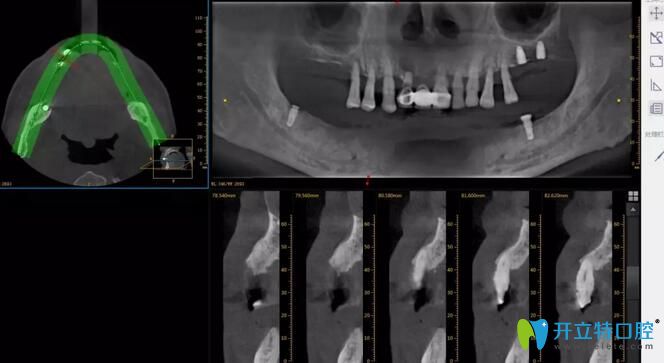

設(shè)備高端:引進(jìn)國(guó)內(nèi)外高端設(shè)備,確保治療質(zhì)量。